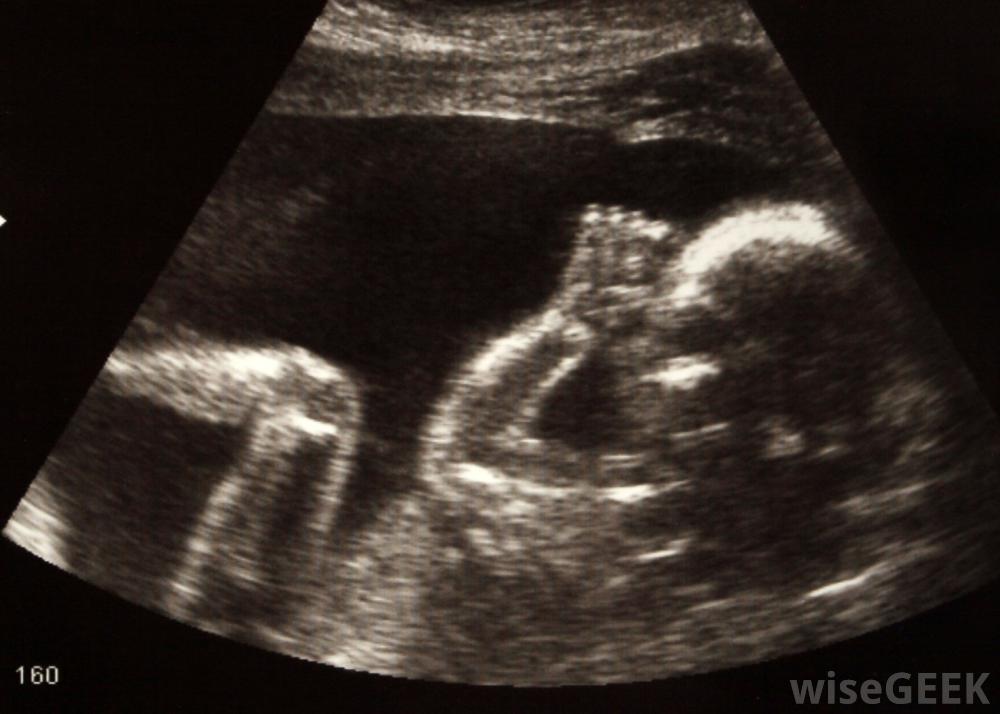

输尿管是连接肾脏和膀胱的管子有输尿管囊肿的病人常有输尿管重复。输尿管囊肿是指输尿管最靠近膀胱的部分的扩大。输尿管进入膀胱的开口也异常狭窄。输尿管囊肿会干扰尿液的正常流动,正常情况下,每个肾脏都有一条输尿管将尿液排入膀胱输尿管重复畸形可能与遗传有关,但确切原因尚不清楚。女性患这种疾病的风险往往比男性高,而且通常女性的两个肾脏也会受到影响。通常情况下,这种情况会被诊断出来这是一种用于产前诊断潜在问题的影像学检查出生后,如果孩子经常遭受尿路感染,可能会怀疑输尿管重复。

在皮肤输尿管造口术中,外科医生会在输尿管与膀胱的连接处切开输尿管。患有尿路感染的儿童可能会被开一个疗程的抗生素。在严重的情况下,他们也可以接受静脉输液。泌尿科医生会评估患者的具体情况和病史,以确定治疗方案。当需要手术时,通常会推迟到患者至少6到12个月大时才进行手术。婴儿的膀胱非常小,这可能会使手术复杂化并增加风险许多输尿管重复畸形可以通过超声诊断如果输尿管重复畸形看起来没有受到这种情况的不良影响,可能不需要治疗。如果输尿管囊肿严重压迫输尿管并导致尿液回流,则可能需要手术引流尿液。在某些情况下,泌尿科医生可能会建议将输尿管同输尿管囊肿一起切除,保留重复的,功能正常的输尿管